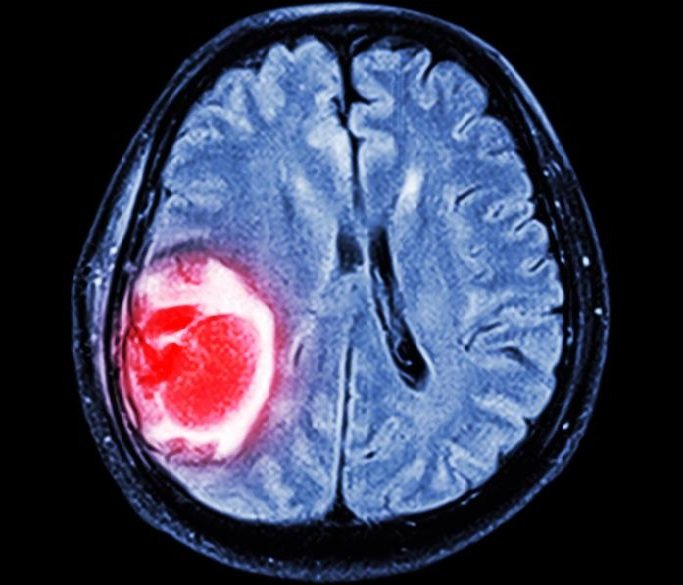

Глиобластома головного мозга(high grade gliomas) — это серьезное коварное заболевание злокачественной природы, которое бесконтрольно развивается в черепной коробке. Этот вид рака формируется из звездчатых глиальных клеток – астроцитов (нейроглиальных звездчатых клеток) и олигодендроцитов (глиальных клеток), которые, в противовес нервным клеткам, могут размножаться. Опухоль быстро пробивается в мозговую ткань, у больного развивается глиобластома, часто почти бессимптомно до последних стадий или метастазирования. Между раковыми и нормальными клетками не существует четкой границы, и именно этот факт делает данный вид рака очень опасным и труднооперабельным.

Расположение глиобластомы (Glioblastoma) может быть различным – она может формироваться в височной и лобной зоне, задевать структуру мозжечка, ствола, иногда клетки спинного мозга. Опухоль вторгается в мозолистое тело, а по истечении времени — в оба полушария. Медики могут наблюдать наличие огромных клеток с парой ядер и ядерный полиморфизм. Так появляются аномальные трансформации в сосудах и артериовенозные свищи, которые напрямую соединяют вены и артерии.

- мультиформная форма (полиморфноклеточная). При ней клетки раковой опухоли очень пластичны и способны перерождаться в различные структуры. Это сильно усложняет лечение, так как каждый вид структуры имеет свою восприимчивость к используемым методам лечения. Из-за сдавливания просвета сосудов могут возникать кровоизлияния и формирование некрозных участков. В клетках опухоли есть большое количество сосудов и артериовенозных фискул. Этот вид раковой опухоли считается недифференцированным (самым злокачественным), она способна достичь огромных размеров, прежде чем ее удастся диагностировать.